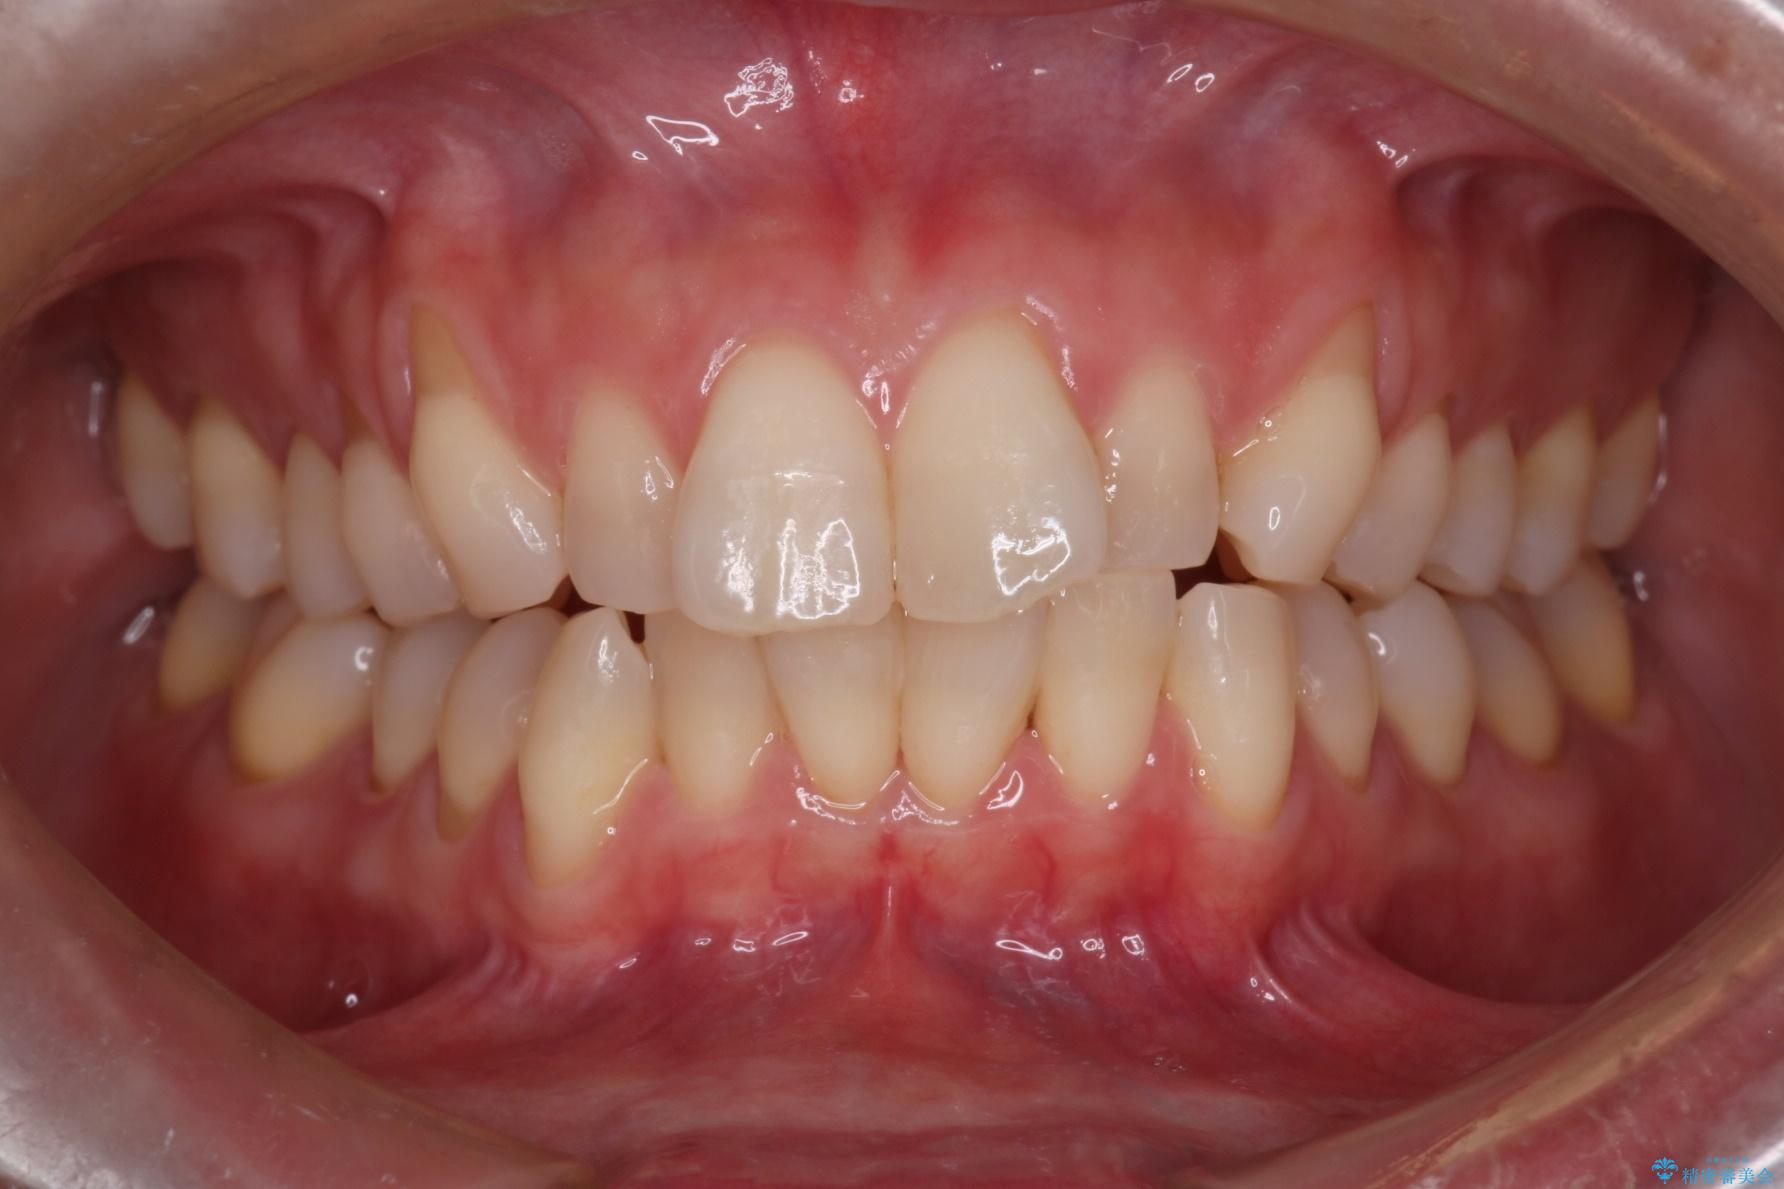

八重歯を治したいとのことで、来院されました。

インビザラインにて、上顎の歯と歯の間をわずかに削り、並べる計画としました。

八重歯を含め並びもきれいになり、かみやすくもなりました。